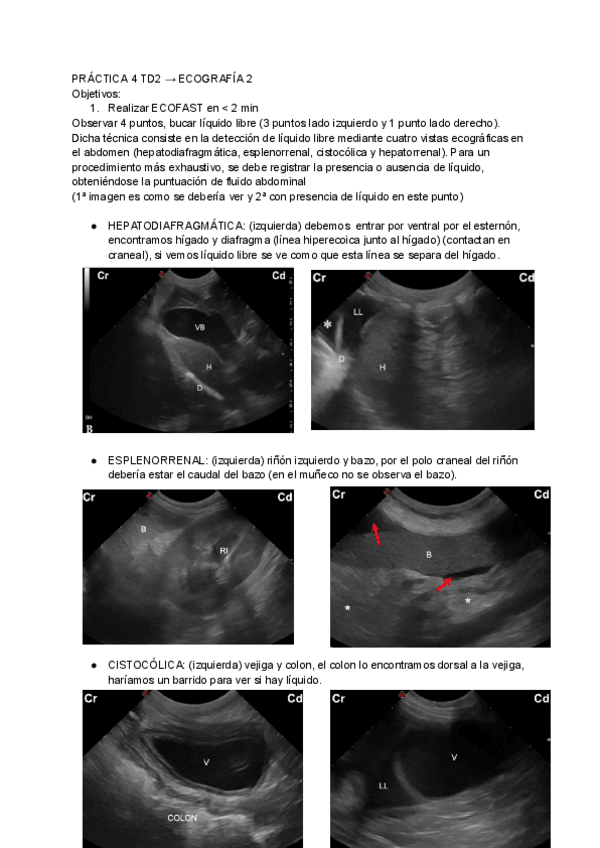

He publicado nuevos practicas de 3º Técnicas de diagnóstico clínico II (Diagnóstico por imagen): PRACTICA-4-TD2-ECOGRAFIA-2.pdf